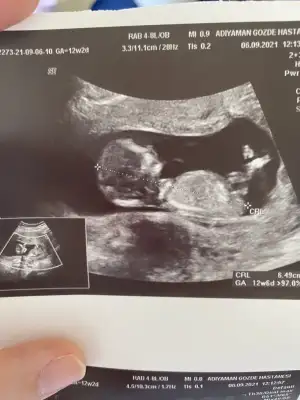

Ikra meyra Ikra meyra canım ilk çocuğumun cinsiyetini bilmiştin buna da bakabilir misin? Şimdiden çook teşekkür ederim🥰

• IMG-20210906-WA0004.webp

IMG-20210906-WA0004.webp

17,8 KB · Görüntüleme: 89

• IMG-20210906-WA0005.webp

IMG-20210906-WA0005.webp

23,6 KB · Görüntüleme: 107